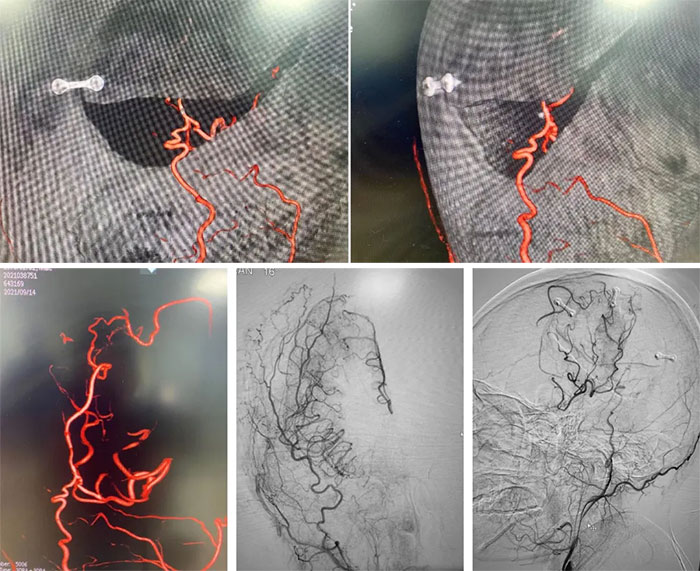

▲ 术后影像显示供血明显改善

脑部外科手术本身就是极度复杂和精细的,往往“牵一发”就“动全身”。而由于患者颅内血管神经密集,手术过程中的细微失误,都可能出现血管出血、神经损伤,造成患者的神经功能障碍。张琪博士在刘春医生、李喆医生协助下,在显微镜下将颅外颞浅动脉游离后引入颅内,采用只有头发丝直径1/3的11-0吻合针线,与直径只有1mm左右的大脑中动脉终支角回动脉行端侧吻合。张琪博士像绣花一样,在10倍的显微镜下一点点地完成了精细操作。经过12针缝合,最终颞浅动脉和大脑中动脉成功吻合。缝合后先撤出远端阻断夹无渗血,随后撤出近端阻断夹,血管吻合良好,无出血,以吲哚箐绿静脉造影后见搭桥血管血流通畅,搭桥成功。整个手术持续5个多小时。术后,患者病情稳定,神志清楚,言语流利,肢体活动显著改善。目前,王先生正在康复中。